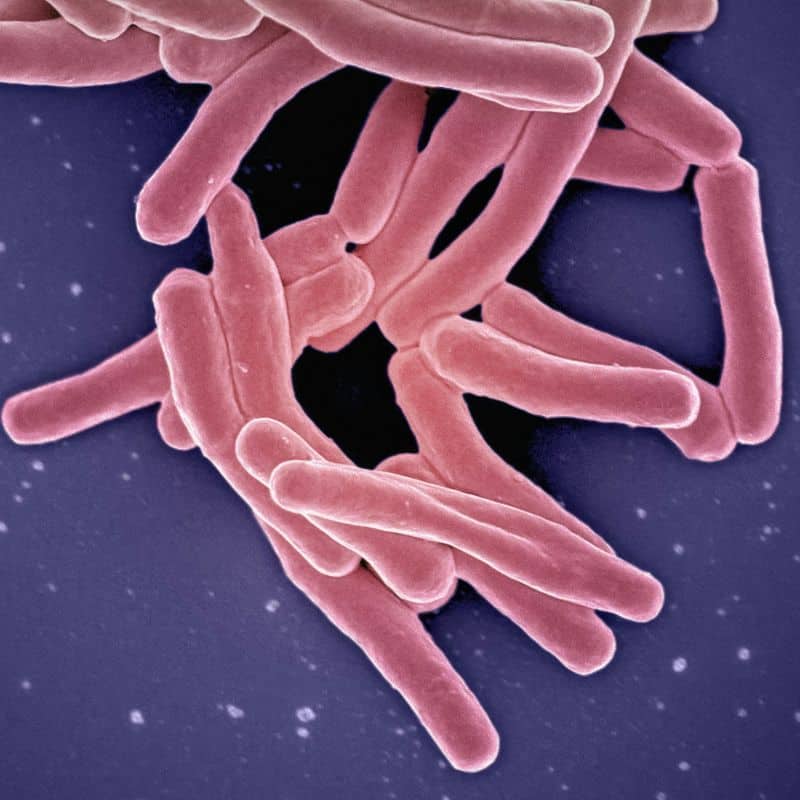

- Hepatitis: es una inflamación del hígado que puede verse propiciada por diversas causas, incluyendo cuadros infecciosos.